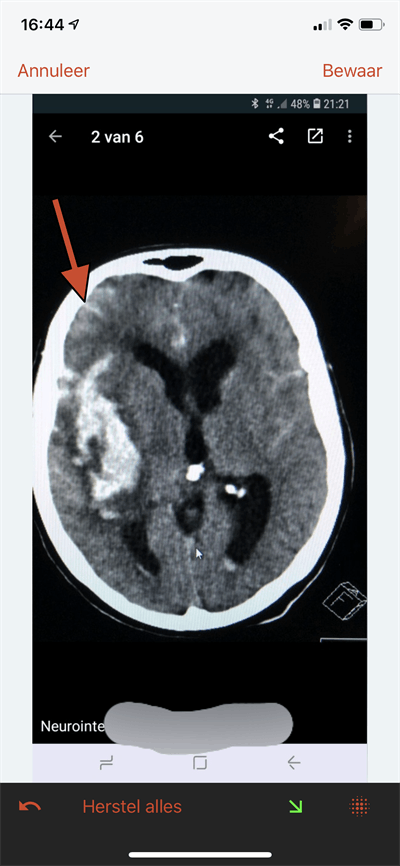

Patients also need to know their images are properly anonymized, he continued. "We know that with today's facial recognition, it is easy for a computer to match a reconstructed image from a CT or MR image of your head to a picture that you published on WhatsApp or the internet."

To avoid such risks, facial data from medical images can be blurred out, but this prevents studies on the nose, eyes, or sinuses to be performed on such altered data. Some data security experts recommend removing all identifying features, including blurring out tattoos on CT scans of the skin, for example. Ratib wonders how much each patient should be informed about what measures are being taken to protect the confidentiality of data.